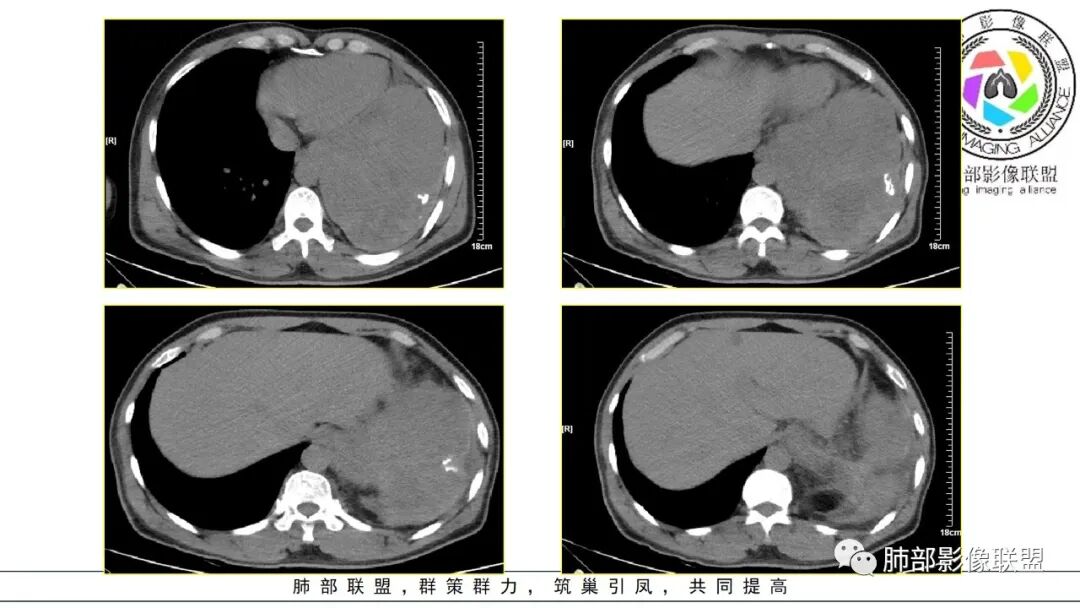

晨读:左肺下叶大肿块,自膈肌向上生长,边缘光滑,周围肺组织受压推移,平扫密度均匀,增强扫描不均匀强化,考虑恶性肉瘤(滑膜肉瘤,成人肺母细胞瘤),鉴别SFT

2.左肺巨大块影,上部边界较清楚,占据胸腔大部,对于左肺,“占据”及“推移”兼而有之,左肺上叶支气管推移狭窄,下叶支气管截断。下肺动脉穿行!

3.病灶密度不均,轻度强化,坏死或液化范围甚大,边界可分辨,部分“壁”可见钙化。

4.病灶紧贴胸壁,胸壁未见栽赃侵入。

1.无论是肺部还是胸腔“巨大实性密度”块影且边界较清楚者,较少为上皮来源的肺恶性肿瘤,而更符合间叶组织来源的肉瘤。

尤其是病程较长(纵隔移位明显),相对破坏力不强,缺乏远处转移证据的,表明其恶性程度并不那么高。